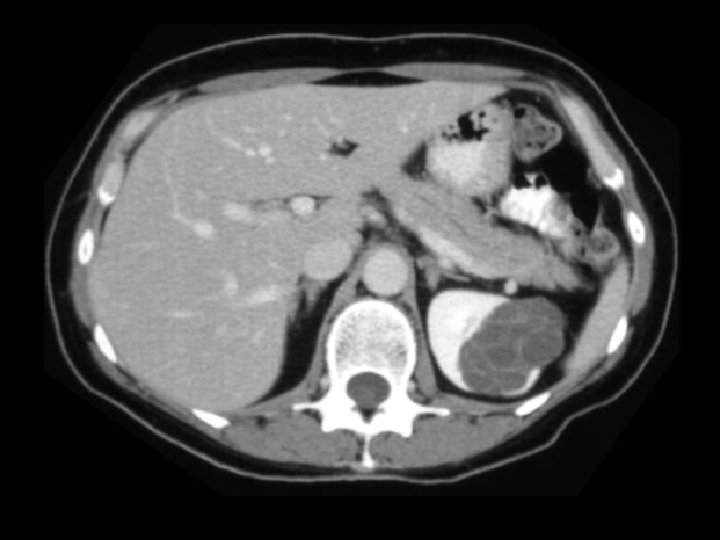

Von-Hippel Lindau • Findings: – Numerous bilateral renal cyst – Solid enhancing right renal mass = RCC • ddx: – NONE! – This is an Aunt Minnie!